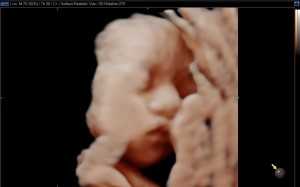

28주 히또초음파예요!

푸히또

2025-10-15